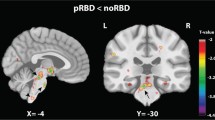

Post hoc t-test analysis revealed the difference between each group pair, setting statistical threshold at p < 0.05 FWE-SVC. iRBD subjects showed a statistically significant decrease of GM volume involving the right orbitofrontal gyrus compared to HC (t = 5.43, local maxima: × 15, y 28, z -14, p-value 0.024) (Fig. 1A), and bilateral precentral gyrus compared both to PD/pRBD and HC (right, t = 4.35, local maxima: × 48, y -3, z 34, p-value 0.001 iRBD vs PD/pRBD, p-value 0.001 iRBD vs HC; left t = 3.60, local maxima: x -20, y -15, z 69, p-value 0.004 iRBD vs PD/pRBD, p-value 0.001 iRBD vs HC) (Fig. 1B); clusters of decreased GM volume including right lingual gyrus (t = 4.17, local maxima: × 15, y -64, z -2, p-value 0.043 PD/pRBD vs HC, p-value 0.033 iRBD vs HC) (Fig. 1C) and fusiform gyrus (t = 4.27, local maxima: × 34, y -3, z -30, p-value 0.003 PD/pRBD vs HC, p-value 0.001 iRBD vs HC) (Fig. 1D) were detected in PD/pRBD and iRBD patients compared to HC. A cluster of increased GM volume in the right superior frontal gyrus was present in iRBD patients when compared to PD/pRBD (t = 4.31, local maxima: × 26, y 21, z 18, p-value 0.001) (Fig. 1E). No other significant differences between groups were found.

Significant clusters of grey matter changes in the post-hoc t-test analysis. A right orbitofrontal. B left and right precentral. C right lingual. D right fusiform. E right superior frontal. *Statistical threshold at p < 0.05 FWE, cluster size > 50 voxels. PD/pRBD = Parkinson’s Disease with probable REM sleep behavior disorder; iRBD = isolated REM sleep behavior disorder; HC = healthy controls

In agreement with previous literature (Chen et al., 2022; Jia et al., 2022; Matzaras et al., 2022; Rahayel et al., 2019), our study showed the presence of decreased GM volume in frontal areas (right orbitofrontal cortex and bilateral precentral gyrus) in iRBD patients compared to both PD/pRBD and HC, and in temporo-occipital regions (lingual and fusiform gyri) in both iRBD and PD/pRBD patients in comparison with HC. Furthermore, we also reported the presence of increased GM volume in superior frontal gyrus in iRBD patients compared to PD/pRBD.

Frontal involvement in iRBD, including orbitofrontal and precentral cortices, has been demonstrated in several studies (Chen et al., 2022; Rahayel et al., 2018a, b). In particular VBM findings have shown a reduced GM volume in iRBD compared to HC in the motor loop, including frontal lobes and these reductions were associated with lower motor performance and clinical iRBD manifestations (Rahayel et al., 2018a). It is well known that iRBD is a major risk factor for PD development (Postuma et al., 2013); the pattern of these structural abnormalities strongly overlaps with cortical regions known to support motor abilities and might suggest that abnormalities in the motor-related cortical areas may already be present before the parkinsonism clinical onset. This hypothesis is also supported by functional MRI studies that have shown abnormalities in the frontal and prefrontal networks in iRBD subjects (Wakasugi et al., 2021), consistent with an early subtle involvement of executive dysfunction providing a promising early biomarker of both cognitive and motor network dysfunctions of alpha-synucleinopathies.

In agreement with literature, we found in both iRBD and PD/pRBD a temporal cortex atrophy involving the fusiform gyrus. Decreased cortical thickness in temporal cortices, including fusiform area, has been found in PD/RBD compared to PD patients without RBD (Rahayel et al., 2019) and in iRBD compared to HC (Campabadal et al., 2019; Rahayel et al., 2015, 2018a, b; Unger et al., 2010). Accordingly, a recent voxel-wise metanalysis including VBM studies, showed a significantly reduced GM volume in the right superior temporal gyrus in PD/RBD, compared to PD without RBD, suggesting the association between the occurrence of RBD in PD patients and atrophy in the temporal areas (Yang et al., 2020). In agreement with these findings, perfusion and metabolism imaging studies demonstrated the presence of changes in metabolism in temporal areas, in RBD patients compared to HC (Ge et al., 2015; Mazza et al., 2006; Vendette et al., 2011). The involvement of temporal areas in RBD and the underlying mechanisms remain to be understood. Temporal and limbic areas are found to be significantly activated during physiological REM sleep (Nir & Tononi, 2010); thus, these abnormalities could reflect a disruption of the normal atonia circuitry leading to the occurrence of RBD behaviors. On the other hand, temporal GM changes could be associated to the RBD-related clinical characteristics of PD patients, including cognitive impairment, spatial information processing and mood abnormalities (Yang et al., 2020). The presence of a similar pattern of structural abnormalities involving temporal regions in iRBD and PD/RBD groups has been previously faced by Pereira and coll (Pereira et al., 2019) suggesting the presence of a high prevalence of future iRBD to PD converters in their sample, meaning that subtle changes were already present in patients with iRBD (Pereira et al., 2019).

Our data also show the presence of decreased GM volume in the posterior regions, involving the lingual gyrus in PD/pRBD and iRBD subjects, compared to HC. Abnormalities in the occipital regions have previously been demonstrated in PD/RBD (Campabadal et al., 2019; Guo et al., 2018; Rahayel et al., 2019). The occipital and frontal connections with the brainstem reticular formation, a core pathological region in RBD, are well known (Jang & Kwon, 2015). Thus, damage in the brainstem reticular formation may cause a potential effect on structures and networks involving the occipital and frontal cortex, to rebalance the abnormalities in the reticular formation (Guo et al., 2018).

Considering all these results, iRBD subjects seem to show a greater involvement of frontal cortical regions than PD/pRBD (bilateral precentral and right orbitofrontal gyri) and to share similar posterior cortical abnormalities with PD/pRBD compared to HC (right fusiform and lingual gyri). As previously demonstrated (Campabadal et al., 2019; Mazza et al., 2006), an anterior (i.e., the orbitofrontal cortex) and posterior (i.e., the parieto-occipital and temporal cortices) pattern of cortical atrophy was consistently described in iRBD subjects (Valli et al., 2022). Taking into account the degree of cortical involvement, we cannot exclude that this could be due to the different RBD duration of iRBD subjects with respect to that of PD/pRBD, as well as to the presence of subjects in the prodromal stages of different synucleinopathies in the iRBD cohort that may convert overtime.

As for the GM volume increase involving superior frontal gyrus in iRBD patients compared to PD/pRBD, this finding is consistent with previous studies reporting the occurrence of volume increases involving cortical (Park et al., 2019) and subcortical regions (Holtbernd et al., 2021), as well as of metabolic increases in frontal cortex by means of the FDG-PET in iRBD patients (Kim et al., 2021). The authors suggest that cortical activations of the frontal areas might produce overactivity in the subcortical regions, such as the caudate nucleus, thus resulting in the expression of excessive movement during sleep in iRBD subjects (Park et al., 2019). Accordingly, the presence of hypermetabolism in the frontal regions, together with hypometabolism in the posterior regions (both representing areas of structural and functional changes), might reflect a co-occurrence of neurodegenerative and compensatory phenomena (Kim et al., 2021). These findings are in agreement with structural/functional data showing changes in connectivity values involving occipital cortices together with the presence of decreased GM volume than HC, and increases in cerebellum and deep grey nuclei (Chen et al., 2022). Therefore, the difference between iRBD and PD/pRBD may be explained by a continuum ranging from “pure” iRBD to a more pronounced brain abnormality as seen in overt PD (Chen et al., 2022; Holtbernd et al., 2021).